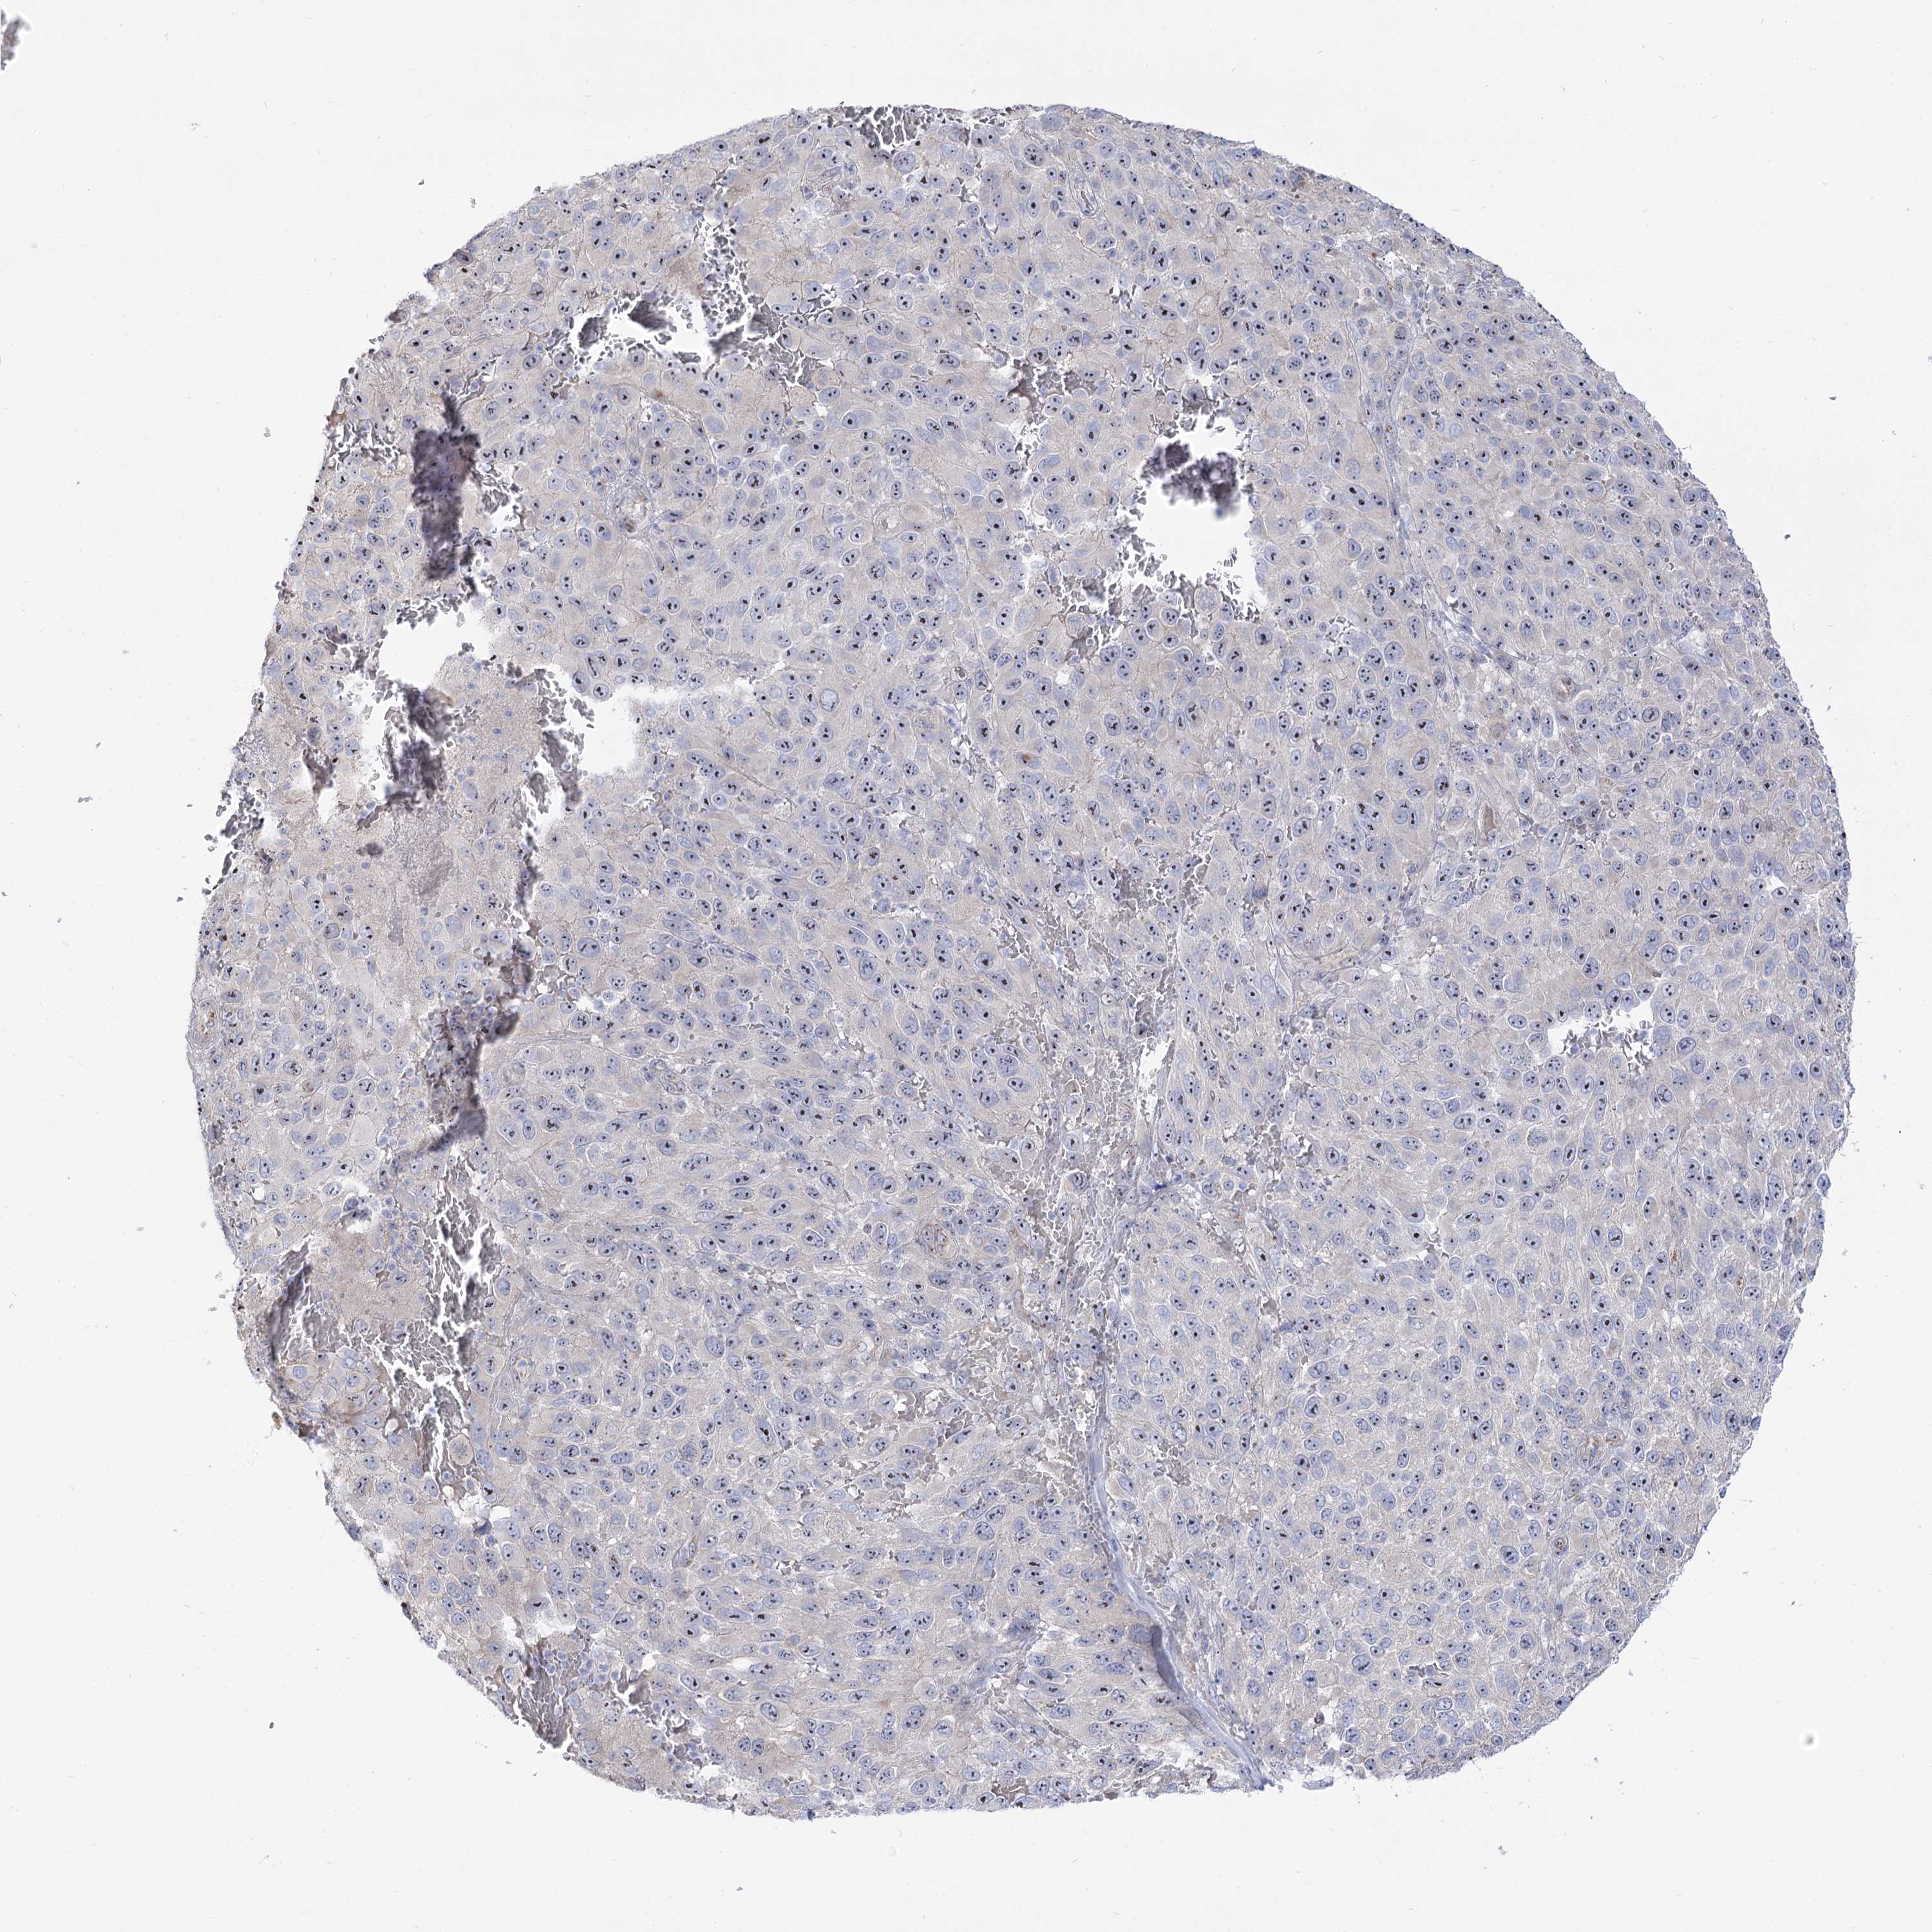

MELANOMA - Protein expressioni

A mouse-over function shows sample information and annotation data. Click on an image to view it in a full screen mode. Samples can be filtered based on level of antibody staining by selecting one or several of the following categories: high, medium, low and not detected. The assay and annotation is described here.

Note that samples used for immunohistochemistry by the Human Protein Atlas do not correspond to samples in the TCGA dataset.

Antibody stainingi

Antibody staining in the annotated cell types in the current human tissue is reported as not detected, low, medium, or high, based on conventional immunohistochemistry profiling in selected tissues. This score is based on the combination of the staining intensity and fraction of stained cells.

Each image is clickable and will lead to virtual microscopy that enables deeper exploration of all samples and also displays staining intensity scores, fraction scores and subcellular localization as well as patient and tissue information for each sample.

Antibody HPA038208

Antibody HPA038209

Malignant melanoma, NOS

Malignant melanoma, Metastatic site